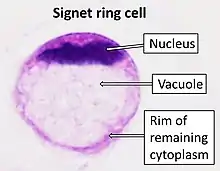

In histology, a signet ring cell is a cell with a large vacuole. The malignant type is seen predominantly in carcinomas. Signet ring cells are most frequently associated with stomach cancer,[1] but can arise from any number of tissues including the prostate,[2] bladder, gallbladder,[3] breast, colon,[4] ovarian stroma and testis.[5]

Appearance

The name of the cell comes from its appearance; signet ring cells resemble signet rings. They contain a large amount of mucin, which pushes the nucleus to the cell periphery. The pool of mucin in a signet ring cell mimics the appearance of a finger hole and the nucleus mimics the appearance of the face of the ring in profile.